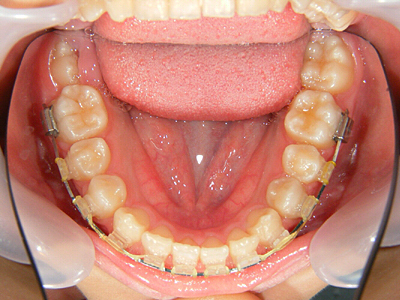

10. 矯正中下顎

下顎は上顎と比較して優成長でしたので、歯列の拡大はせずジスキングのみでスペースを確保して詰めています。年齢が12歳でこれから中学への就学に伴って下顎の成長が加速される懸念がありますので、上下顎の成長バランスを考慮します。